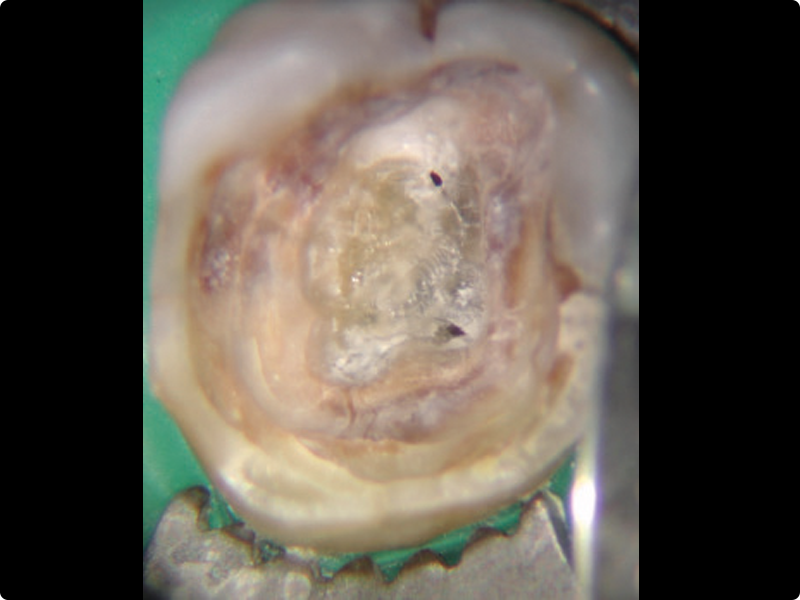

• Redefining a proper access cavity

• Management of calcified canals

• Mechanical shaping of the canal body in continuous rotation and reciprocation on extracted teeth with access cavities already prepared by the participant (ideally at least 3 single-rooted and 3 multi-rooted teeth, both upper and lower, with access cavities prepared)